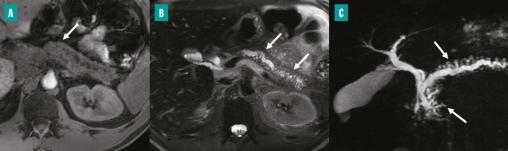

La séquence en pondération T1 avec suppression du signal graisseux (A) montre un hyposignal T1 diffus de la glande pancréatique. La séquence en pondération T2 avec suppression du signal graisseux (B) montre une dilatation irrégulière (flèches), sans sténose du conduit pancréatique principal. La séquence de cholangio-pancréatographie-IRM (C) confirme la présence d’une dilatation diffuse et irrégulière du conduit pancréatique principal, ainsi qu’une dilatation en « flammèche » des conduits pancréatiques secondaires. Une atrophie diffuse et modérée de la glande pancréatique est également observée.